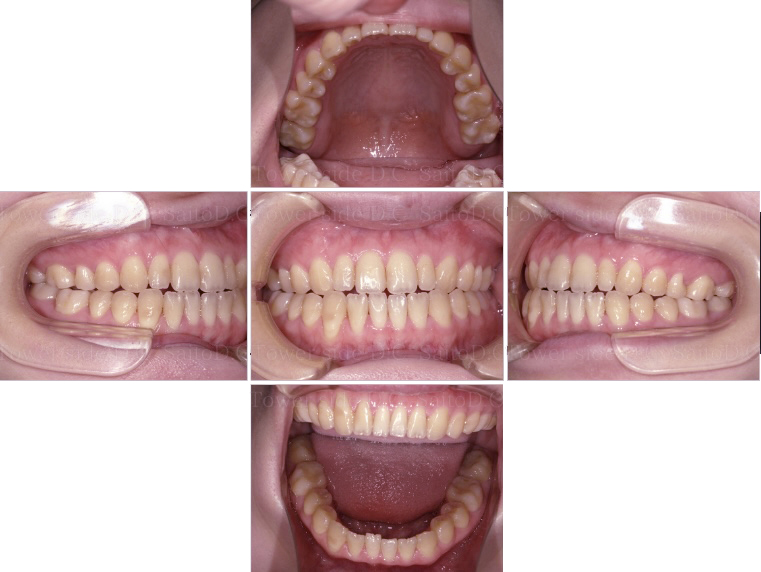

症例5CASE 5

|20代(女性)|

マウスピース矯正

症例(施術前)

症例(施術後)

主訴 八重歯が出ている

状況

• 前歯部叢生

• 上顎犬歯は低位唇側転位(八重歯)

• 口唇閉鎖不全有

治療費 1,030,700円(税込)(自由診療)

治療期間 2年8ヶ月

治療内容 14.24.34.44EXTを抜歯。矯正開始後1年経たずして遠方へお引越しとなったが、患者様のご希望があり当院でマウスピース矯正を継続。叢生、八重歯、臼歯部噛み合わせは改善され、その後保定装置(リテーナー)を使用し安定している。

リスク

• 歯根呼吸や、歯根の成長が阻害される可能性。

• 歯髄が壊死する可能性 歯の痛み、顎の痛み、虫歯、歯周病、矯正器具により口腔粘膜の傷、喋りにくさが生じる可能性。

• 矯正治療後は、リテーナーを使用しないと歯の位置に後戻りが生じる可能性。